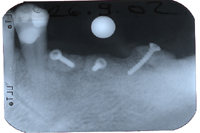

Um den Kieferkamm zu verbreitern, habe ich aus der hinteren Unterkieferregion drei Knochenstücke entfernt und sie mit je einer 9 bzw. 7 mm langen Schraube vorne seitlich fixiert (Abb. 3). Nach einer fünfmonatigen Einheilungszeit wurden die drei Fixationsschrauben entfernt und gleichzeitig zwei Implantate gesetzt (Abb. 4). Da der Knochen transversal üppig breit war, konnte ich zwei Straumann Implantate mit dem grössten Durchmesser von 4.8 mm setzen. Die Metallkeramikbrücke wurde vier Monate später zementiert.